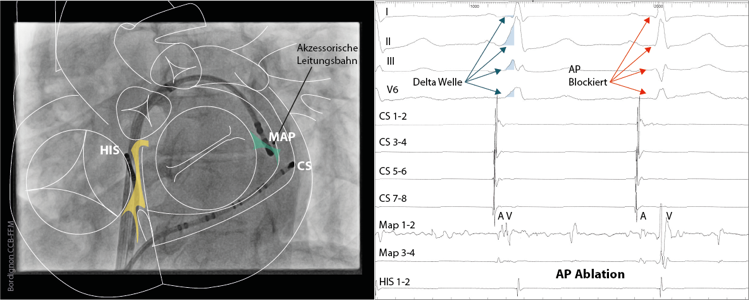

akz-leitungsbahn

(Abb. 1) Schematische Darstellung des Herzens über einer Röntgenaufnahme in LAO Projektion. Typische Katheterpositionen im Herzen im Rahmen einer Katheterablation einer linksseitigen akzessorischen Leitungsbahn. Der Zugang zum linken Herzen erfolgt hier nach einmaliger transseptaler Punktion.